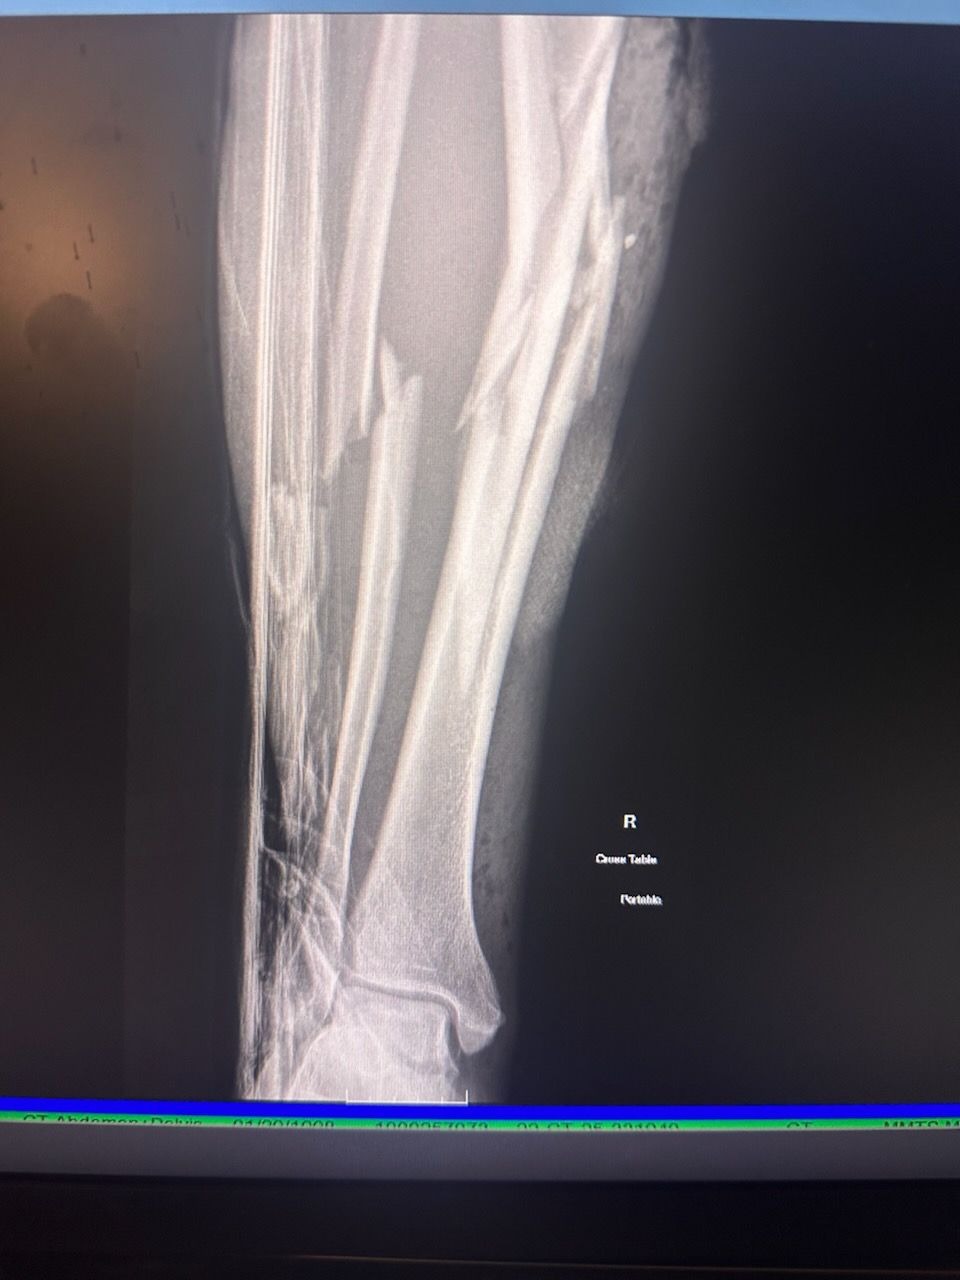

On June 12, 2025, I suffered a devastating accident during my usual after work visit to South Fork river. A 4,000 pound boulder rolled over my leg, crushing my tibia and fibula and nearly severing my lower leg. Alone and with no cell service, I had to fight for my life, crawling, climbing, and driving myself miles in excruciating pain to find help. I made it to cell signal and reached my long time best-friend and co-parent, Kim Latos. She happened to be close by and arrived to find me in a puddle of blood and slipping into unconsciousness. I had lost over half my blood once we arrived at the ER.

I was airlifted to Redding Mercy Medical Trauma Center for emergency surgery, where a titanium rod was inserted to save my leg. Days later, I was hospitalized again with a severe, antibiotic-resistant form of pneumonia I contracted during surgery, bringing me close to death for the second time in two weeks.